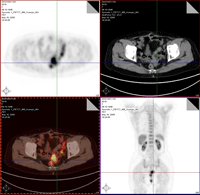

1.陰道超聲檢查 可測量卵巢的大小和形態。對有HBOCS傾向的婦女發現卵巢增大,應引起重視,必要時及時腹腔鏡檢查和活檢以期早發現卵巢癌,陰道超聲檢查對發現較小的、無症狀的卵巢贅生物較為敏感。

2.彩色都卜勒超聲血流圖 測定卵巢血供後血流情況,有助於鑑別卵巢良惡性腫瘤,主要測定脈衝指數(PI)以pI值1.0為界,如小於該數值提示為惡性

3.血清CA125測定 卵巢上皮性癌,特別是卵巢漿液性癌,80%以上CA125值升高(>35U/ml),晚期者則90%升高一般推薦每年檢測1次血清CA125以提高對有HBOCS傾向婦女卵巢癌的發現率。

癌症監測:有遺傳性乳腺癌-卵巢癌綜合徵的家族成員有必要進行終身癌症監測,監測內容包括:①18~21歲起每月1次乳腺自檢;25~35歲起每年或每半年1次由臨床醫師對乳腺進行檢查;25~35歲起每年1次乳腺攝片。②25~35歲起每年或半年1次的盆腔檢查,陰道超聲檢查血清CA125測定,彩色血流都卜勒觀察卵巢血流情況。